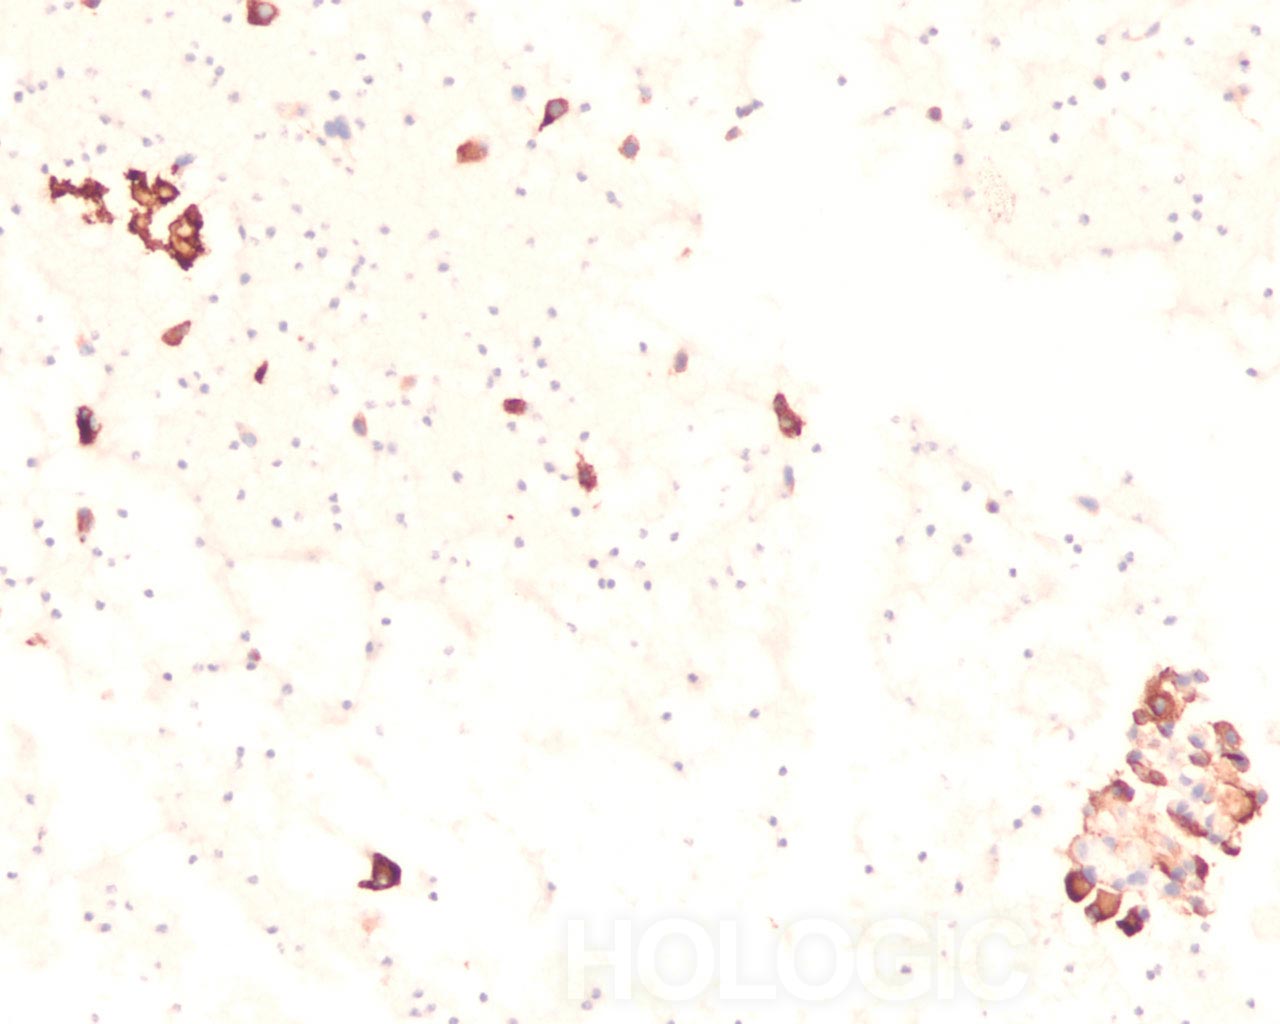

Celblokken verschaffen een stabiel platform voor immunohistochemie. Immunohistochemie voor calcitonine wordt aanbevolen om een medullair schildkliercarcinoom te bevestigen [1]. het immunohistochemisch onderscheid tussen een papillair schildkliercarcinoom en folliculaire neoplasmen heeft geen groot succes gehad [12]. In het algemeen is het zo dat als cellen nucleaire veranderingen ontwikkelen die op papillair schildkliercarcinoom lijken, de cellen markers hebben van papillair schildkliercarcinoom, inclusief positieve kleuring voor cytokeratine 19 en HBME. HBME. [13, 14]. Het onderscheid tussen papillair schildkliercarcinoom en reactieve veranderingen wordt in dergelijke gevallen bepaald door de grootschaliger architecturele kenmerken die soms duidelijk aanwezig zijn in celblokken. De toekomstige ontwikkeling van markers die de diagnostische categorieën van folliculaire laesies in FNA kunnen onderscheiden, vereist vermoedelijk een stabiel platform voor immunohistochemisch of moleculair onderzoek. In paraffine ingebedde celblokken verschaffen een dergelijk platform. We illustreren een nieuwe toepassing van immunokleuring met CD34 die de specifieke diagnose van een insulair type slecht gedifferentieerd schildkliercarcinoom.